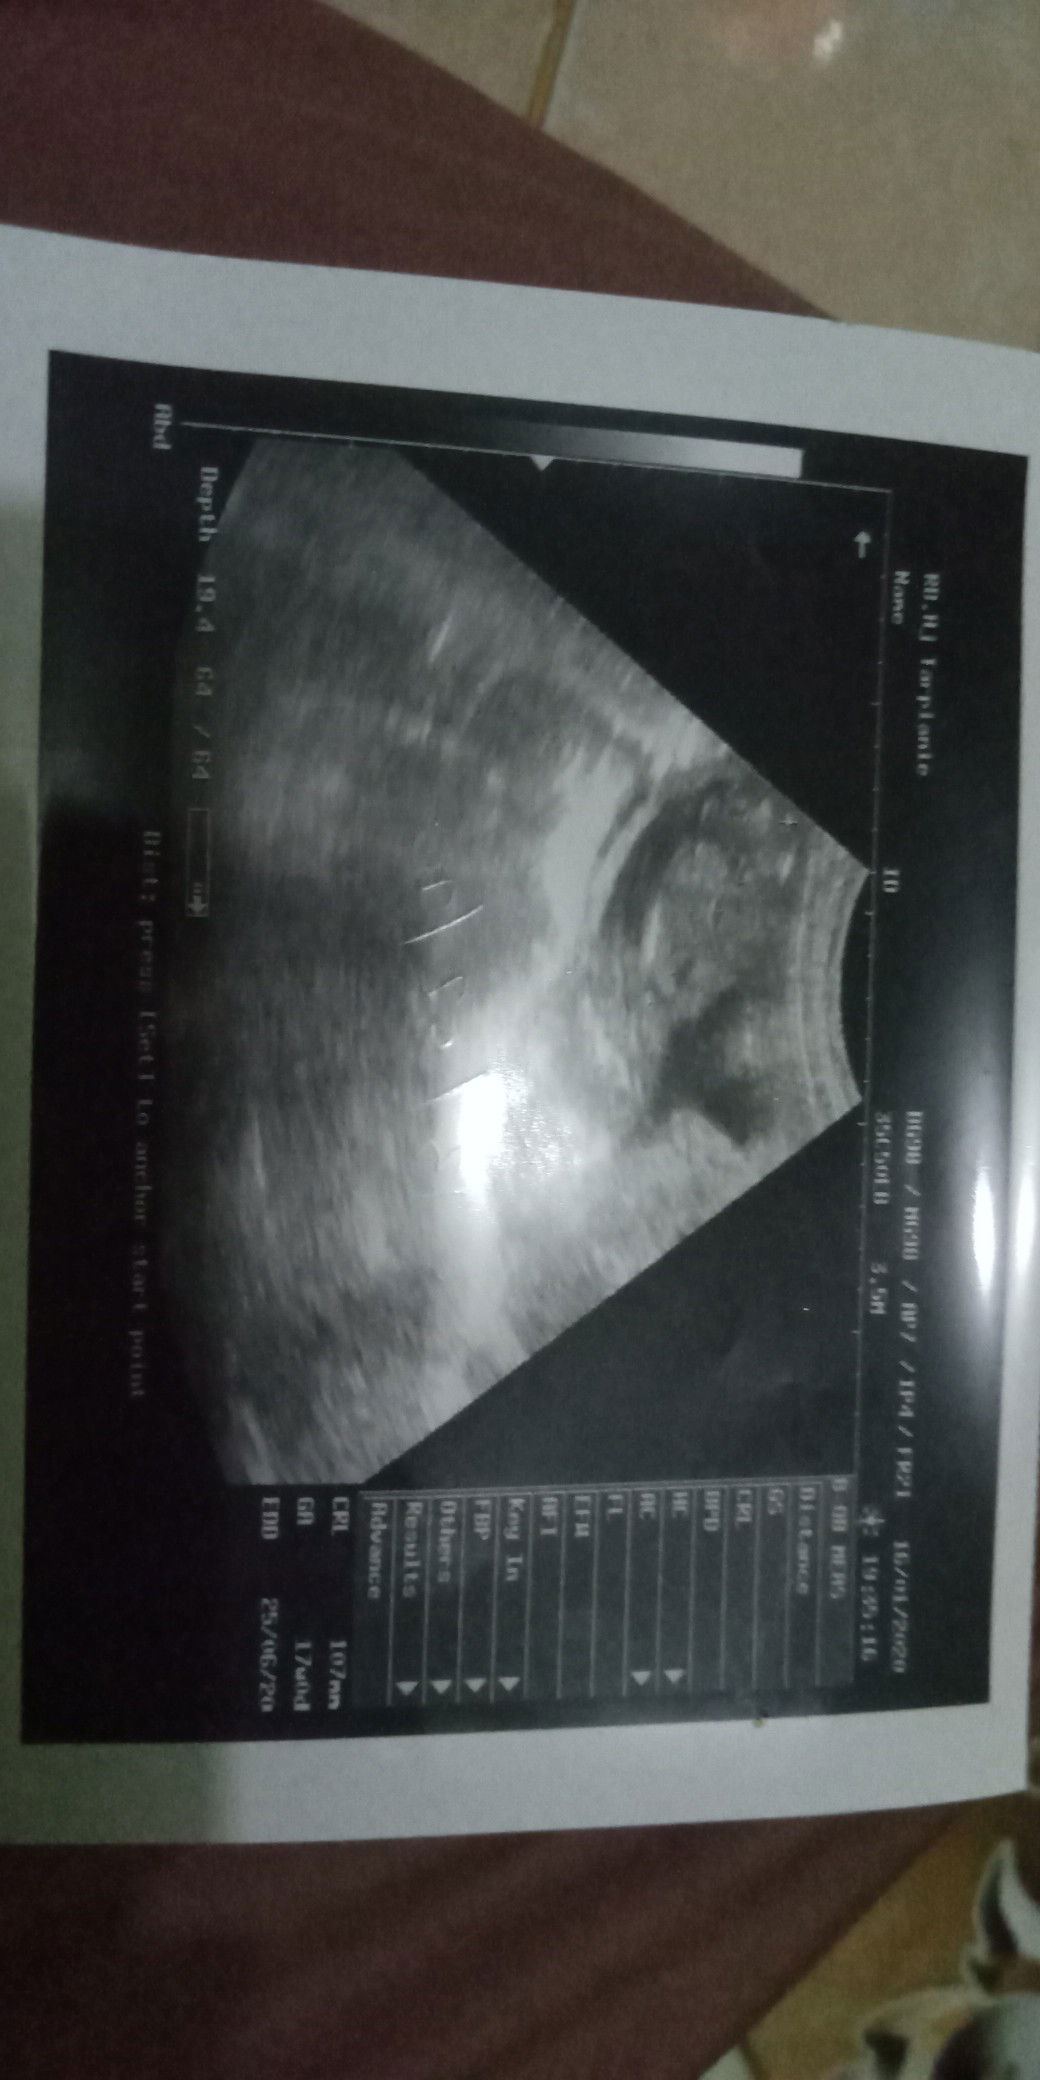

bayiku umur 17minggu

Apa kelamin bayi saya

Apakah sehat bayi saya